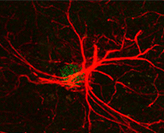

Stroke discovery

New brain wave of thinking in stress and stroke response